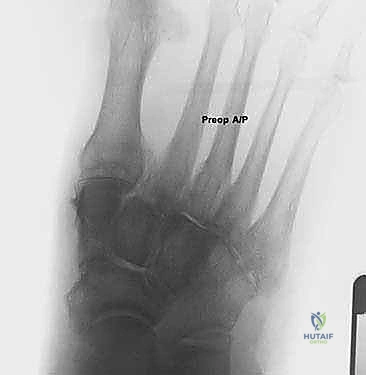

كسور العظم السمسمي لإبهام القدم: دليل شامل للتثبيت الداخلي الدقيق مع الأستاذ الدكتور محمد هطيف